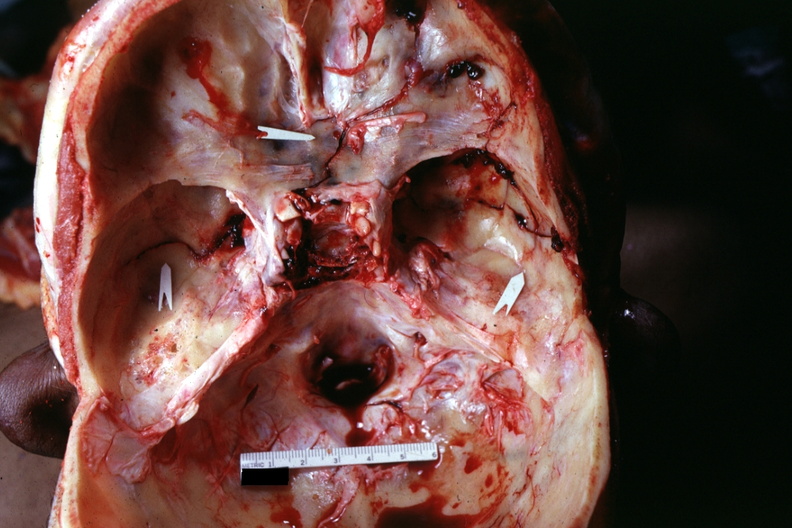

GROSS: HEAD: Bone, calvarium: Basilar Skull Fracture: Gross natural color multiple fractures very well shown

- basilar skull fracture, bone, calvarium, gross, head